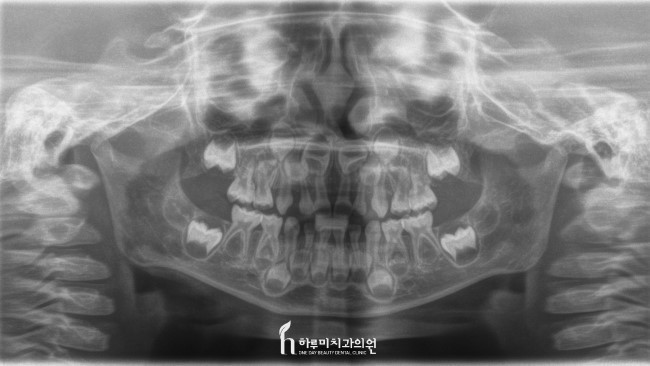

유치는 해부학적 형태가 영구치와는 다를 뿐만 아니라 생리학적으로도 큰 특징이 있다. 가장 현저한 차이점은 계승치가 발육함에 따라 치근이 생리적으로 흡수되어 영구치와 교환된다는 것이다. 이 교환의 시기와 순서는 영구치열의 형성에 커다란 영향을 주는 인자이다.

유치의 치질과 구조에 있어서도

상아질은 영구치보다 얇고 또 치아의 외형에 비해 치수강이 차지하는 비율이 크다. 이 때문에 우식의 진행이 빠르고 치수가 감염되기 쉽다. 그러므로 치관 수복 시에도 와동의 형태나 깊이 등에 주의할 필요가 있다. 유치의 색조는 청백색을 띠고 있으며, 또 법랑질의 경도가 영구치보다 낮기 때문에 교모되기 쉽다.

유치 치수강의 형태는 치아의 외형과 거의 일치하고 있으며, 치수강이 차지하는 비율은 영구치보다 크다.

치수각의 돌출이 현저하다. 특히 근심치수각이 현저하게 높다.